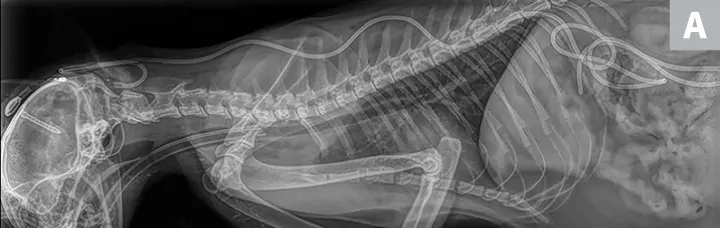

Sternally recumbent Chihuahua with IV catheter in place.

FIGURE 1

Chihuahua with a dome-shaped head caused by congenital hydrocephalus